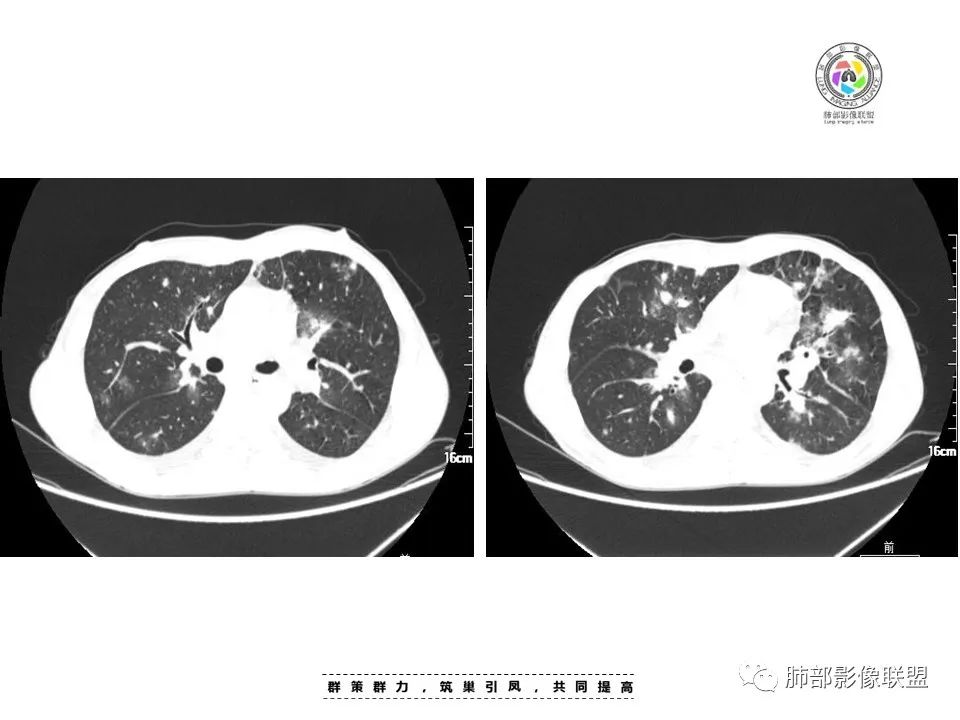

中年男人患者,发热纳差,乏力伴皮疹1月,体温38.4℃,全身暗紫色丘疹,CD4明显降低,双肺多发斑片结节影,周围伴有晕征,有沿支气管血管束分布趋势,无坏死,无空洞,淋巴结增大不明显,考虑机会性感染性病变,马尔尼菲篮状菌病?结核?鉴别淋巴瘤,血管炎(GPA)。

多发结节,肿块,边缘可见晕征,向心性分布,胸膜下病变轻,总体还是气道分布的病变

周一晚读病例:男性45岁,发热、纳差,全身散在暗紫色皮疹,结合CD4,符合HIV;肺部影像表现:两肺散在实性结节及磨玻璃密度影,实性结节伴晕征,部分沿支气管血管束分布,支气管血管束增粗,以两肺下叶为著,类似火焰征,双侧胸腔少量积液;首先考虑卡波西肉瘤,鉴别淋巴瘤增值性病变,淋巴瘤样肉芽肿/淋巴瘤,最后挂上马尔尼菲青霉菌病。

两肺多形态小斑片影,上轻下重沿支气管血管分布,双肺下叶小片状,密度不均匀,含模糊的GGO影,右肺中、下叶与左肺舌叶及下叶病灶累及中轴及小叶间隔增厚,双肺叶间胸膜增厚及伴随粟粒结节,双侧胸腔对称性少量积液,纵隔脂肪间隙混浊(示淋巴回流受阻),慢性发病,发热,乏力,皮肤皮诊表现,贪血,WBC,CD4+低,脾增大,肺感染疾病:马尔尼菲篮状菌,并发TB待排,支气管镜肺泡灌洗液和结核X-Pert检查。

中年男性,发热、全身散在暗紫色丘疹,查CD4+T细胞64个/ul,临床信息提示AIDS并发卡波西肉瘤;CT提示双肺多发实性结节影及毛玻璃结节,部分呈点晕征,右上肺大姐姐边缘膨隆、分叶伴晕;双下肺结节沿支气管血管束分布,中轴间质增粗,部分支气管堵塞,叶间裂结节状增厚,部分结节胸膜下分布,可疑局部小叶间隔增厚,肺部病变呈淋巴分布特点,结合临床肺部病变考虑肺卡波西肉瘤,鉴别淋巴瘤。

2.本例双肺小叶间隔增厚明显,多发结节影及片状实性密度影,沿血管支气管束分布为主,两侧较为对称,病灶多环以磨玻璃晕,边界不清。

双侧胸腔少量积液。双肺门及纵隔未见明确肿大淋巴结,纵隔结构间隙模糊。

3.有学者将这种具有沿双肺支气管束分布的实性密度片影描述为“火焰征”,认为具有一定特征性,单就影像表现而言,这种影像表现也可以见于其他病损或多种病理改变的叠加。

如马尔尼菲篮状菌感染,HIV患者总会联想到它!同样可以出现双肺多发结节影、片影及磨玻璃影,结节影边界也可以较为清楚(甚至可以有点类似结核那种肉芽肿结节),磨玻璃影常见于灶周出血等等。尽管临床实践中马尔尼菲篮状菌感染似乎更多表现为淋巴增大及网质内皮系统损害(如肝脾改变)以及较特有的带有脐凹的皮疹等等。